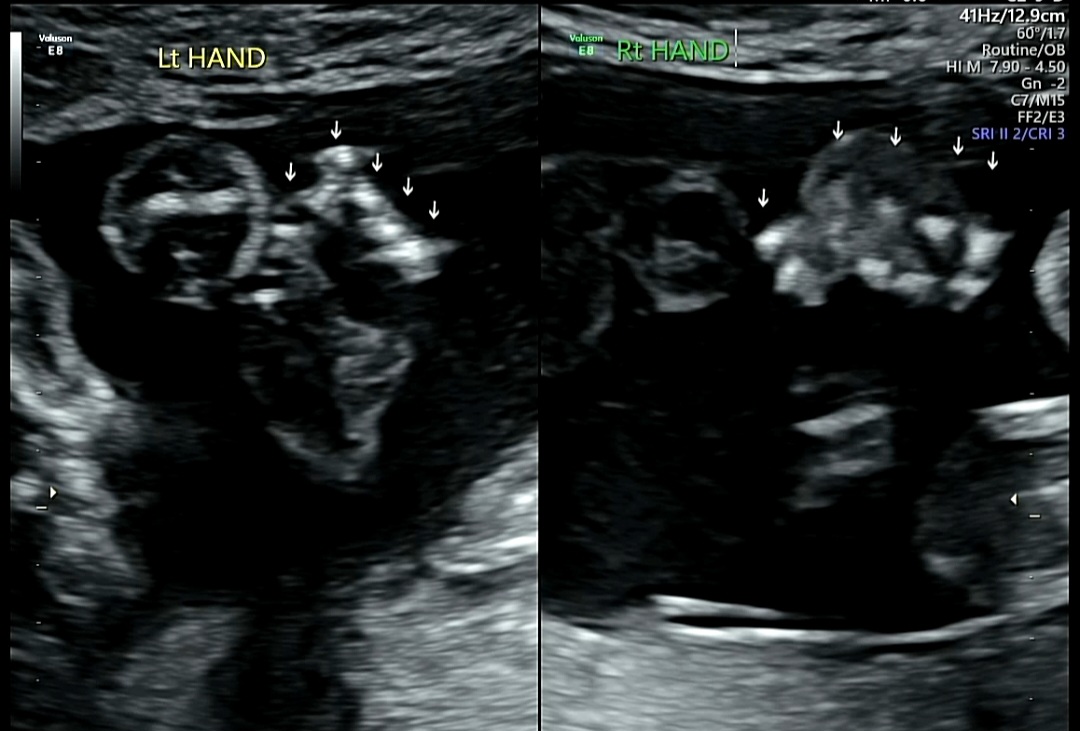

3) Lt HAND(왼쪽 손)/Rt Hand(오른쪽 손)/Lt FOOT(왼쪽 발)/Rt FOOT(오른쪽 발)

양쪽 손가락, 발가락 모양 및 개수 확인

꿀떡이가 주먹을 쥐고 있는 바람에 손가락 개수 세는 것도 쉽지 않았다.